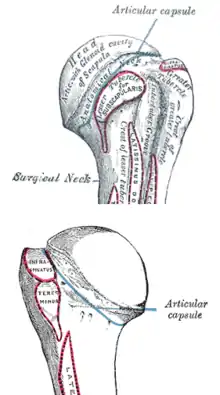

The shoulder joint consists of the glenoid cavity of the scapula and the head of the humerus. It as an extremely mobile joint that is stabilized by surrounding soft tissues such as the joint capsule, muscles, and ligaments.[11] The greater and lesser tuberosities are bony landmarks of the proximal humerus and serve as attachment sites for musculature.

The anterior and posterior humeral circumflex arteries branch off of the axillary artery to provide the majority of the blood supply to the proximal humerus.[11]

The axillary nerve courses inferior to the shoulder joint and innervates the deltoid and teres minor muscles. It also provides sensation at the skin overlying the shoulder. This nerve is the most commonly injured nerve in proximal humerus fractures due to its location close to the proximal humerus.[12]

Muscles that attach to the proximal humerus and can cause a deforming force on fracture fragments include the pectoralis major, the deltoid, and the rotator cuff muscles.[11]